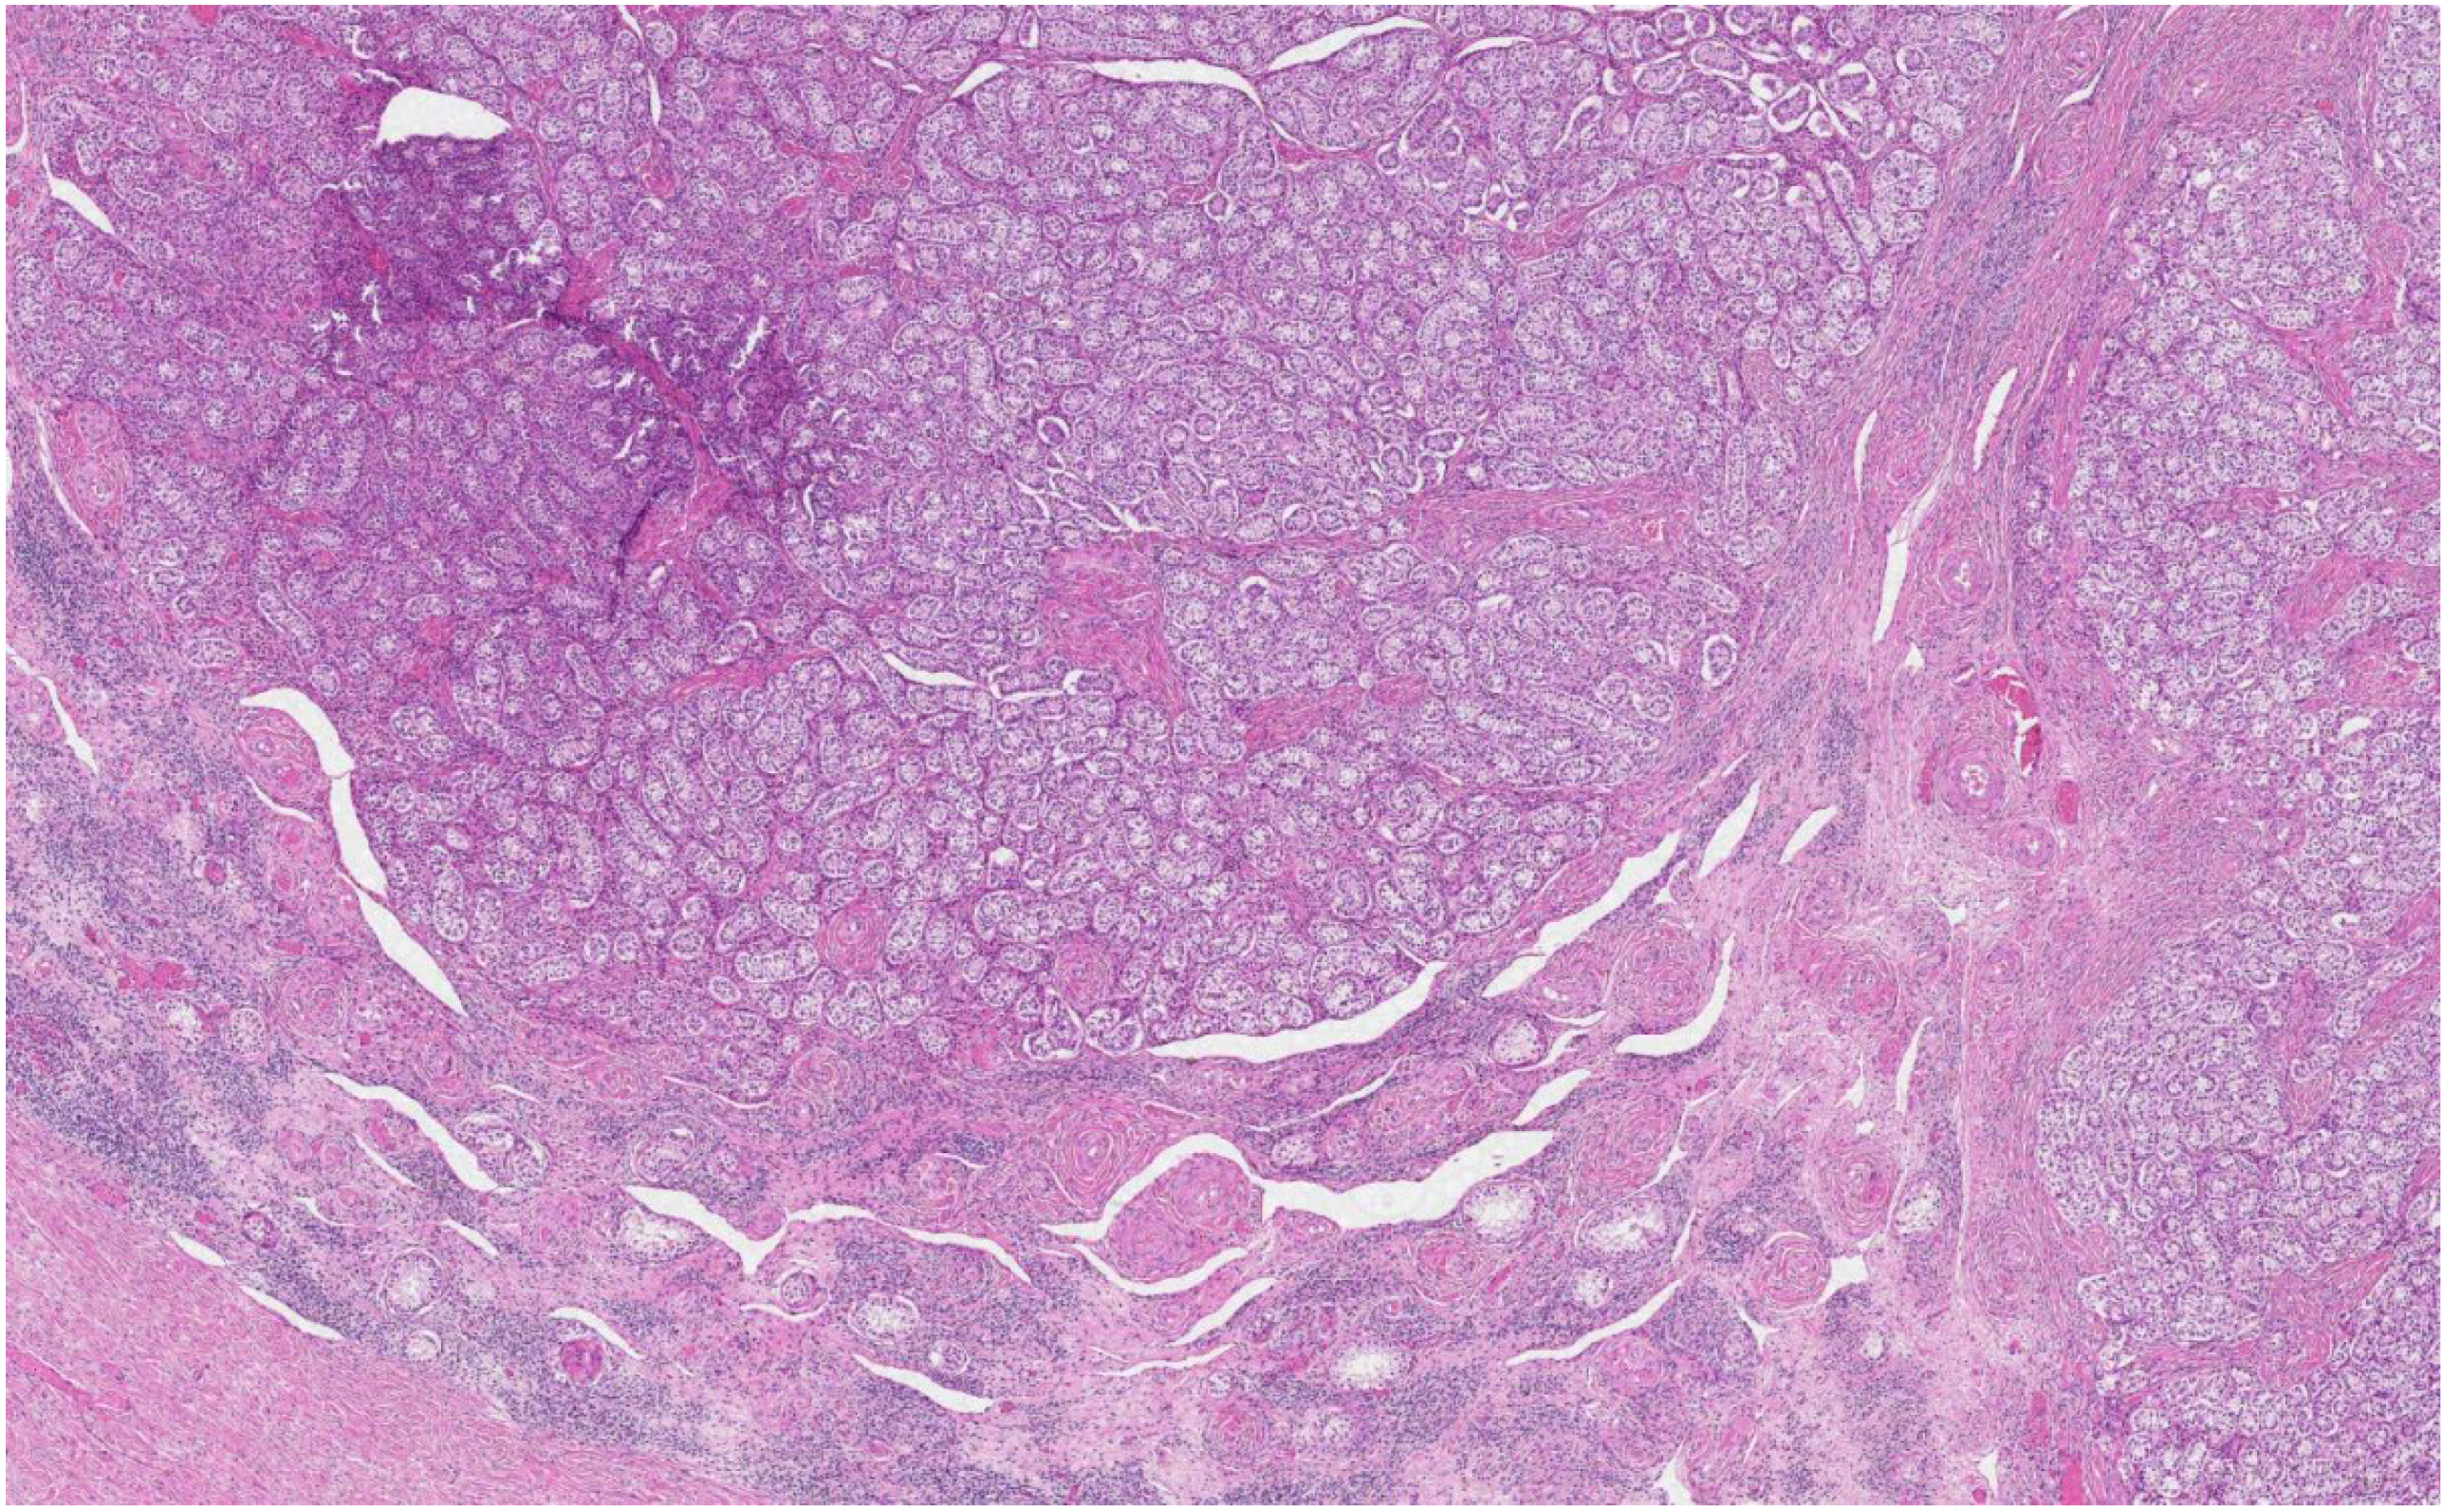

The histological analysis of the patient’s removed gonads revealed that there were hypoplastic testicles, which is a clinical sign of androgen insensitivity syndrome (Figure 3, Figure 4, Figure 5 and Figure 6). After the operation, testosterone analysis was repeated-hormone level significantly decreased to 0.83 nmol/L, which is a normal female-range value for a woman at that age.

Figure 3. Microscopic examination revealed testes, formed by small tubules with mostly absent lumen, composed of Sertoli cells surrounded by fibrous stroma, or stroma resembling ovarian stroma, between tubules and separately at the periphery of tubules-nodules and small nests of Leydig cells with abundant eosinophilic cytoplasm and round nuclei (H&E staining, ×30).